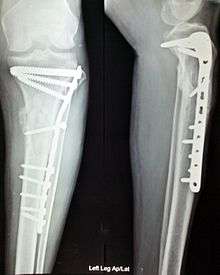

The use of intramedullary rods to treat fractures of the femur and tibia was pioneered by Gerhard Küntscher of Germany. This made a noticeable difference to the speed of recovery of injured German soldiers during World War II and led to more widespread adoption of intramedullary fixation of fractures in the rest of the world. However, traction was the standard method of treating thigh bone fractures until the late 1970s when the Harborview Medical Center in Seattle group popularized intramedullary fixation without opening up the fracture.